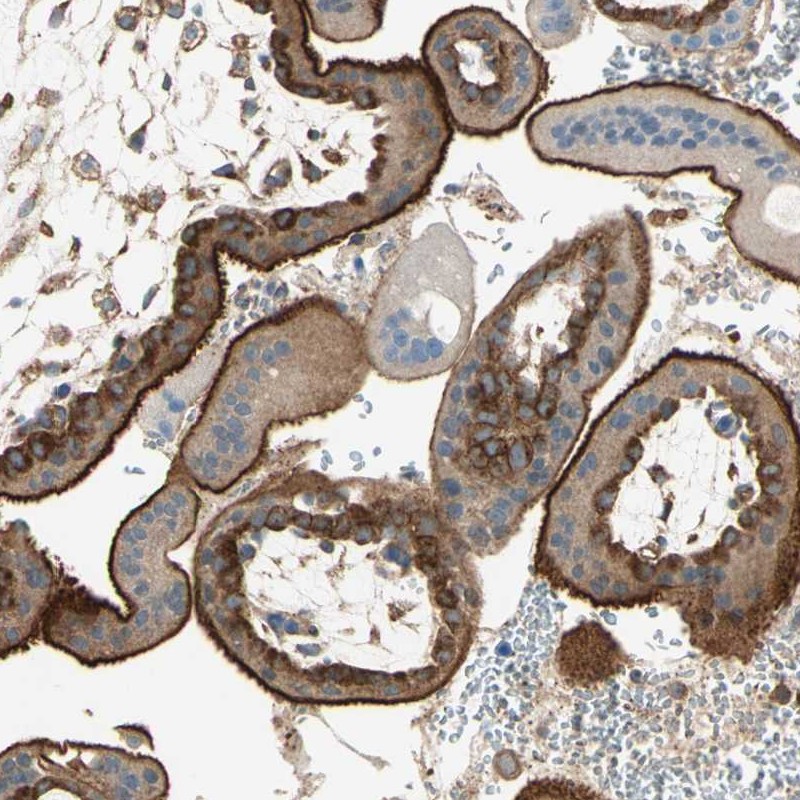

Immunohistochemical staining of human placenta shows strong membranous positivity in trophoblastic cells.